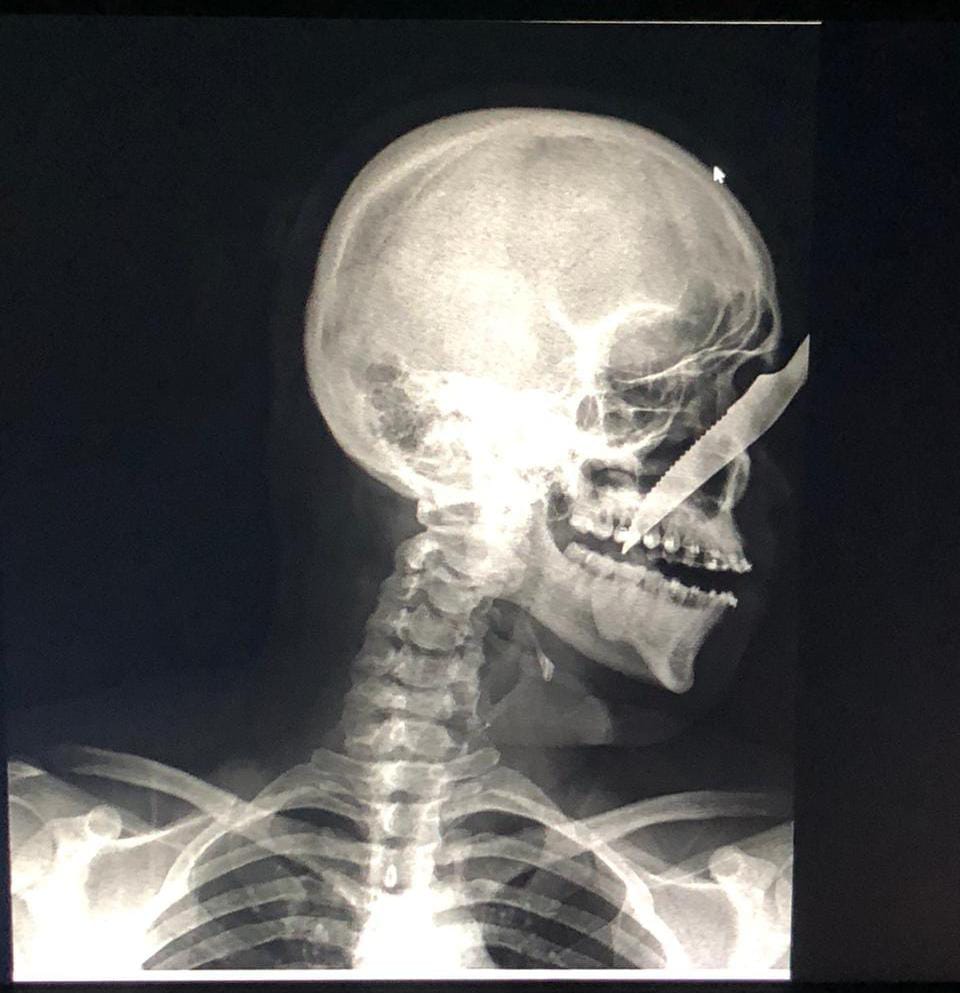

Homem fica com faca cravada no rosto após ataque no interior do AM

Alberto Carvalho de Oliveira, 25, levou uma facada no rosto que ficou cravada no nariz na última sexta-feira (17). O autor da facada foi identificado como André Luís Benevides Carvalho, 35, que estava bêbado quando fez o ataque no município de Carauari (a 788 quilômetros a oeste de Manaus).

Alberto foi socorrido e encaminhado para o hospital do município onde passou por cirurgia e André  foi levado para a delegacia pela Polícia Militar, passou por audiência de custódia e foi liberado.